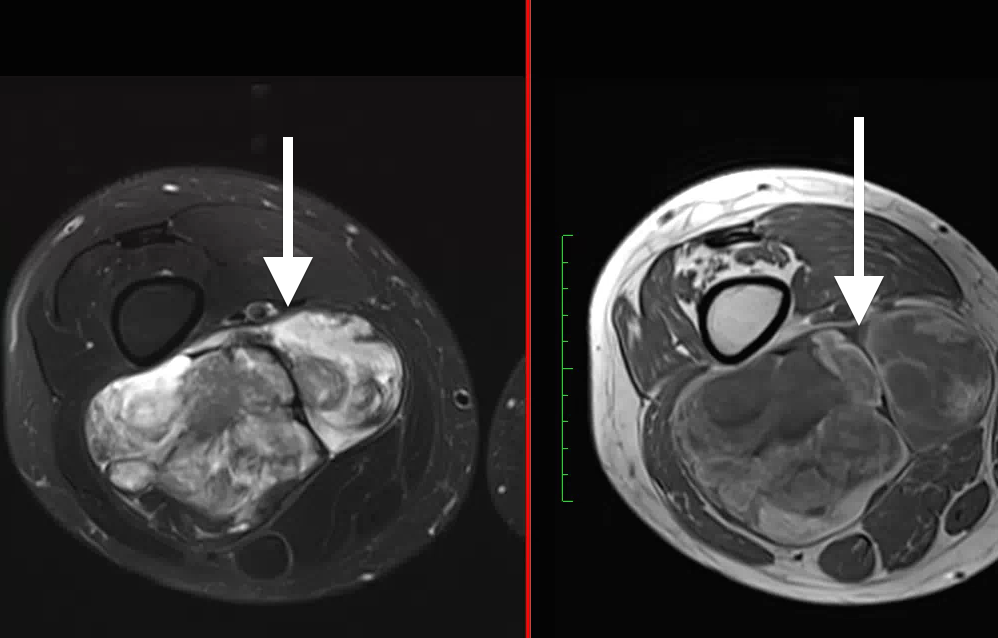

биопсия. Из опухоли необходимо взять образец ткани. Если опухоль труднодоступна, для направления иглы к опухоли можно использовать методы визуализации, такие как МРТ или КТ.

Визуализирующие исследования также могут помочь определить размер и количество опухолей. Эти тесты также могут определить, были ли поражены близлежащие органы и ткани.